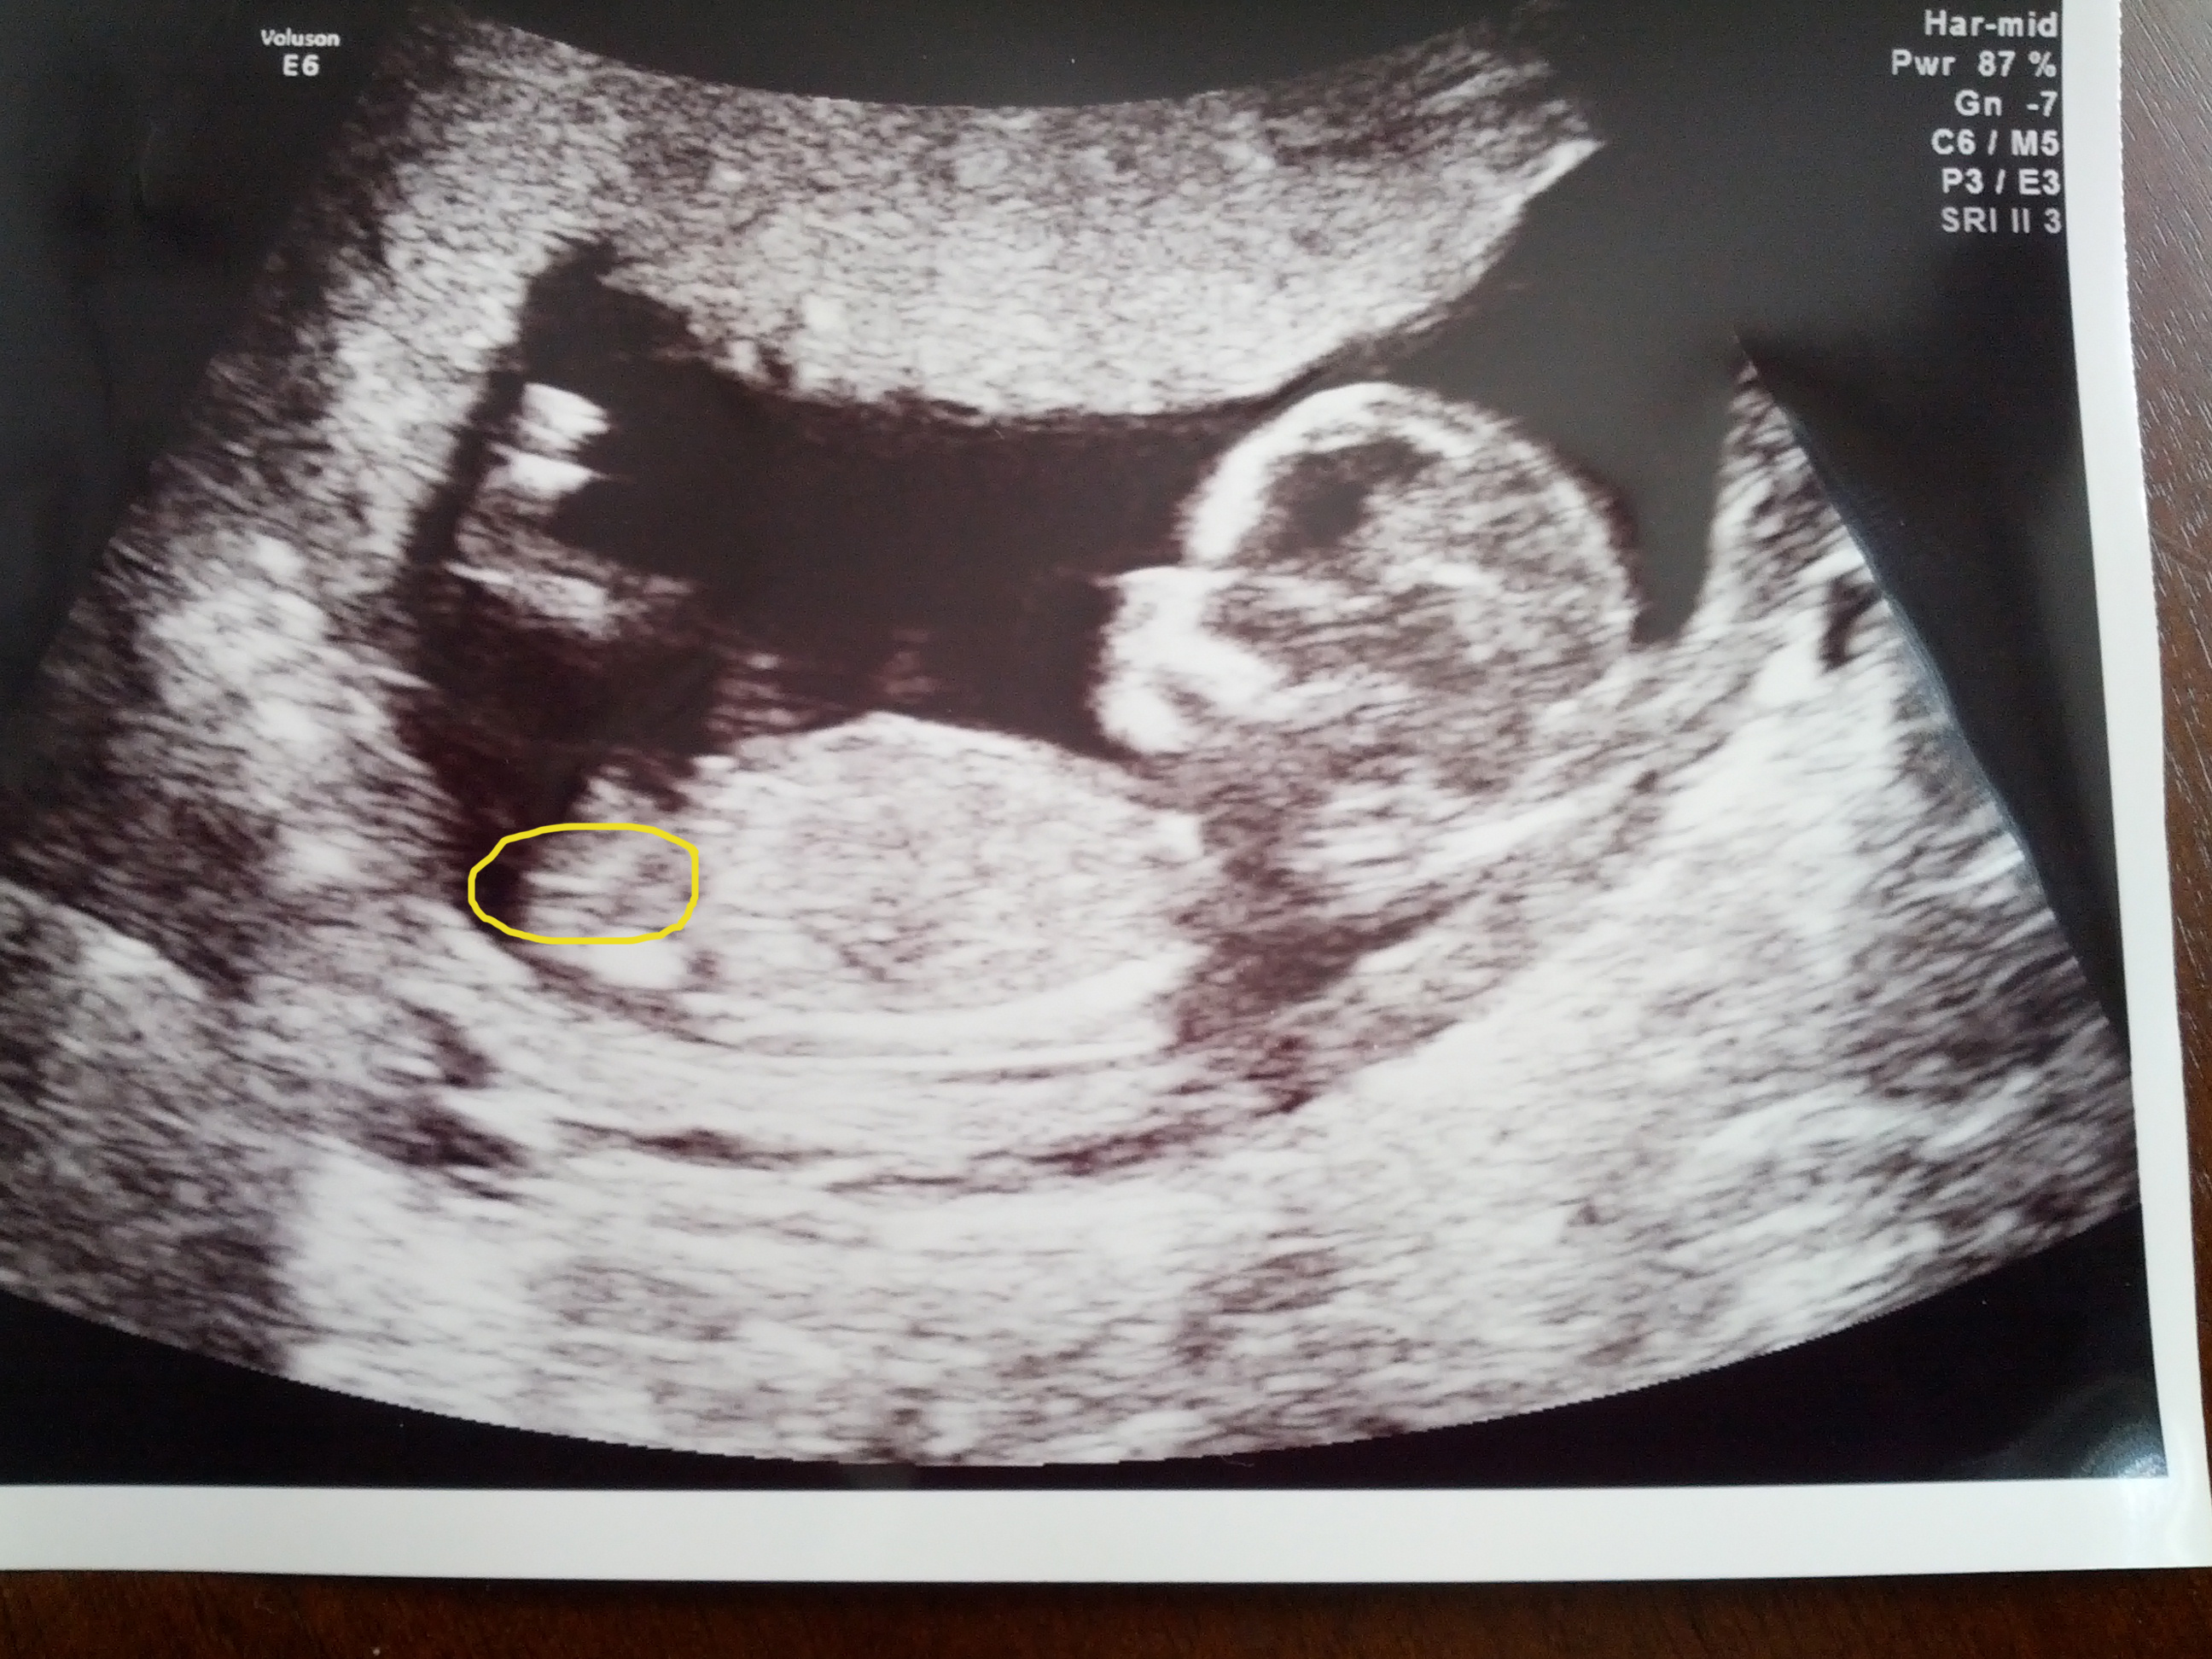

Here they are....very obvious to me and the tech. She did a potty shot and there was something between the legs that she was 50/50 on and that it wasn't as prominent as most boys she sees. Then, the nub said it all.

Attachment 5296